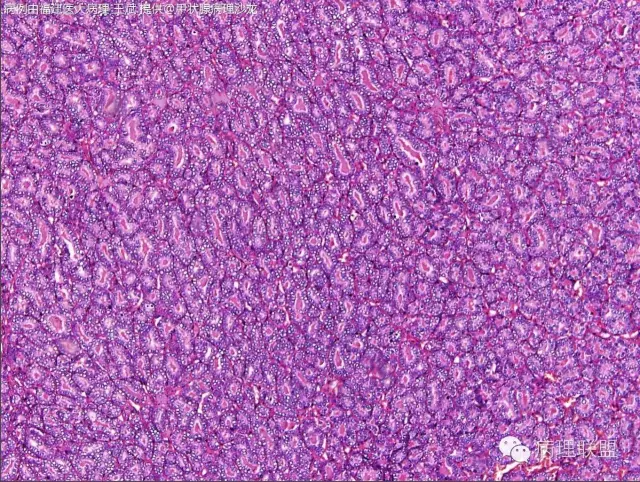

女性,20岁,甲状腺肿物(本病例由福建医大病理 王斌提供,致谢!)

Encapsulated follicular variant papillary thyroid carcinoma with capsular invasion——如总体为包裹性滤泡性病变的话(图一提示,但只一部分)

我担心的包膜侵犯是不是切破了造成的假象,我补一个MASSON染色看看

@福建医大病理 王斌 ,我觉得不是切破,上方也有浸润的趋势。

昨天下午中美读片我也提到了,如果是浸润性包裹型,生物学行为、分子特点和微小浸润性的FTC是一样的,所以不需要太纠结。

CD56、Galectin3、HMBE-1阴性,CK19灶阳

GGALECTIN3 和HMBE1 均为阴性

如果严格按照WHO分类的定义,符合经典乳头状癌和滤泡癌的病例不多,大多数高分化癌病例的组织学病变处于经典乳头状癌和经典滤泡癌,这两个极型之间的位置。